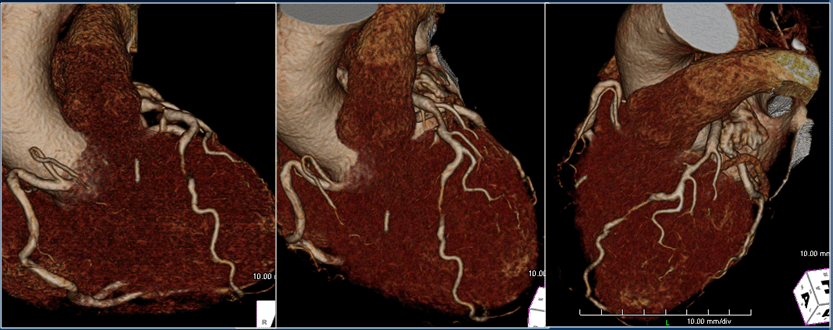

Kawasaki disease

Cherry Kim, Korea University Ansan Hospital